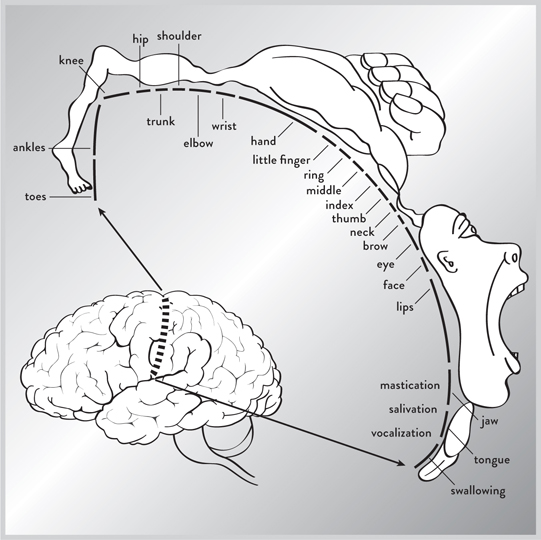

彭菲尔德博士注意到,当他用电极刺激皮层的某些部分时,身体的不同部分会产生反应。他突然意识到,他可以在皮层的特定区域和人体之间建立粗略的一对一对应关系。他的绘图如此准确,以至于至今仍在以几乎未经修改的形式使用。它们立即对科学界和公众产生了影响。在一个图表中,你可以看到大脑的哪个区域大致控制哪种功能,以及每种功能的重要性。例如,由于我们的双手和嘴巴对生存至关重要,相当多的脑力被用于控制它们,而我们背部的传感器几乎没有任何反应。

图1. 这是由怀尔德·彭菲尔德博士创建的运动皮层地图,显示大脑的哪个区域控制身体的哪个部分。

到1950年代和60年代,已经可以创建一个粗略的大脑地图,定位不同的区域,甚至识别其中一些区域的功能。